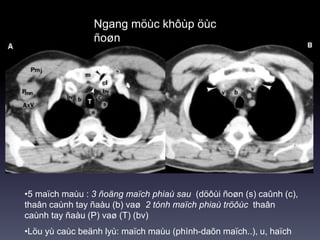

Ngang möùc khôùp öùc

ñoøn

•5 maïch maùu : 3 ñoäng maïch phiaù sau (döôùi ñoøn (s) caûnh (c),

thaân caùnh tay ñaàu (b) vaø 2 tónh maïch phiaù tröôùc thaân

caùnh tay ñaàu (P) vaø (T) (bv)

•Löu yù caùc beänh lyù: maïch maùu (phình-daõn maïch..), u, haïch

Ngang möùc khôùpöùc ñoøn •5 maïch maùu : 3 ñoäng maïch phiaù sau (döôùi ñoøn (s) caûnh (c), thaân caùnh tay ñaàu (b) vaø 2 tónh maïch phiaù tröôùc thaân caùnh tay ñaàu (P) vaø (T) (bv) •Löu yù caùc beänh lyù: maïch maùu (phình-daõn maïch..), u, haïch